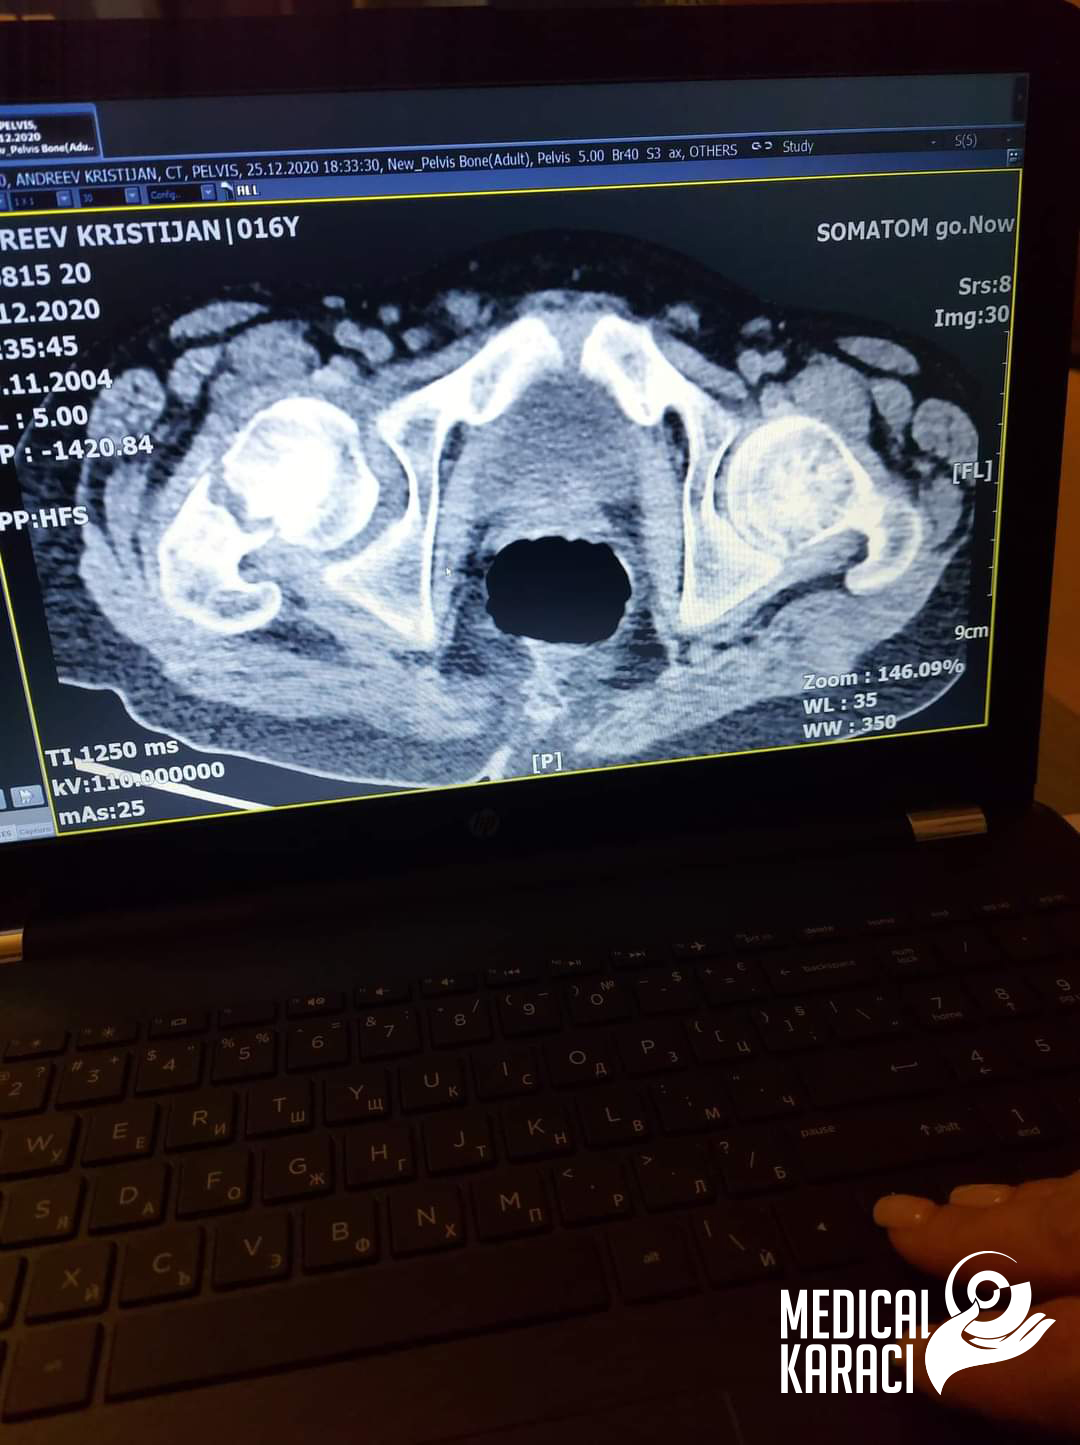

Kristijan è un bambino di 17 anni che soffre di una forma molto grave di autismo e di epilessia; nel dicembre 2020 è caduto e gli hanno sparato. Koga site in Macedonia kazuvaa ni deka nemoze da ho operiraat i deka nema nikogash veke da zastane na noge i da odi jas ne se otkazav, no nitu ti mila moja Zvezdelina Kara i Karaci Tours Medical denonokno istrazuvashe, him barashe i him najdobroto za Kristijan !Kristijan blagodarenie na te i na Prof. Dr. Mustafa Kürklü ZASTANA NA NOZE I ODI 🙏🙏Neznam kako da ti se zablagodaram za se shto napravi i pravish za Kristijan, za celata organizacija vo bolnicata Ospedale Memorial Bahcelievler per tutto il tempo in cui siete con noi. Ecco perché gioite e combattete insieme a noi🙏